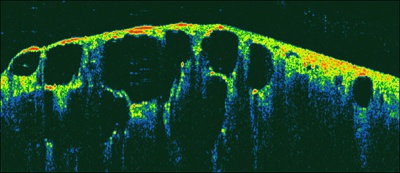

OCT, effectively an optical biopsy method, can offer better resolution (2-3 microns) and more detail in real time than either conventional CT or ultrasound imaging, says Tomophase, adding that the technique has been shown to differentiate between malignant and benign tissues in pulmonary nodules.